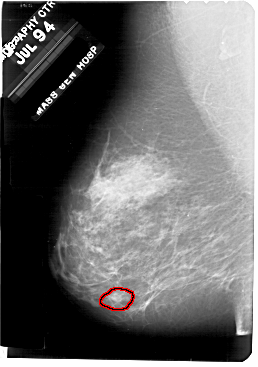

A_1707_1.LEFT_CC

LEFT_CC LINES 5491 PIXELS_PER_LINE 3781 BITS_PER_PIXEL 12 RESOLUTION 43.5 OVERLAY

FILE: A_1707_1.LEFT_MLO.OVERLAY

TOTAL_ABNORMALITIES 1

ABNORMALITY 1

LESION_TYPE CALCIFICATION TYPE PLEOMORPHIC DISTRIBUTION CLUSTERED

ASSESSMENT 4

SUBTLETY 1

PATHOLOGY BENIGN

TOTAL_OUTLINES 1

BOUNDARY